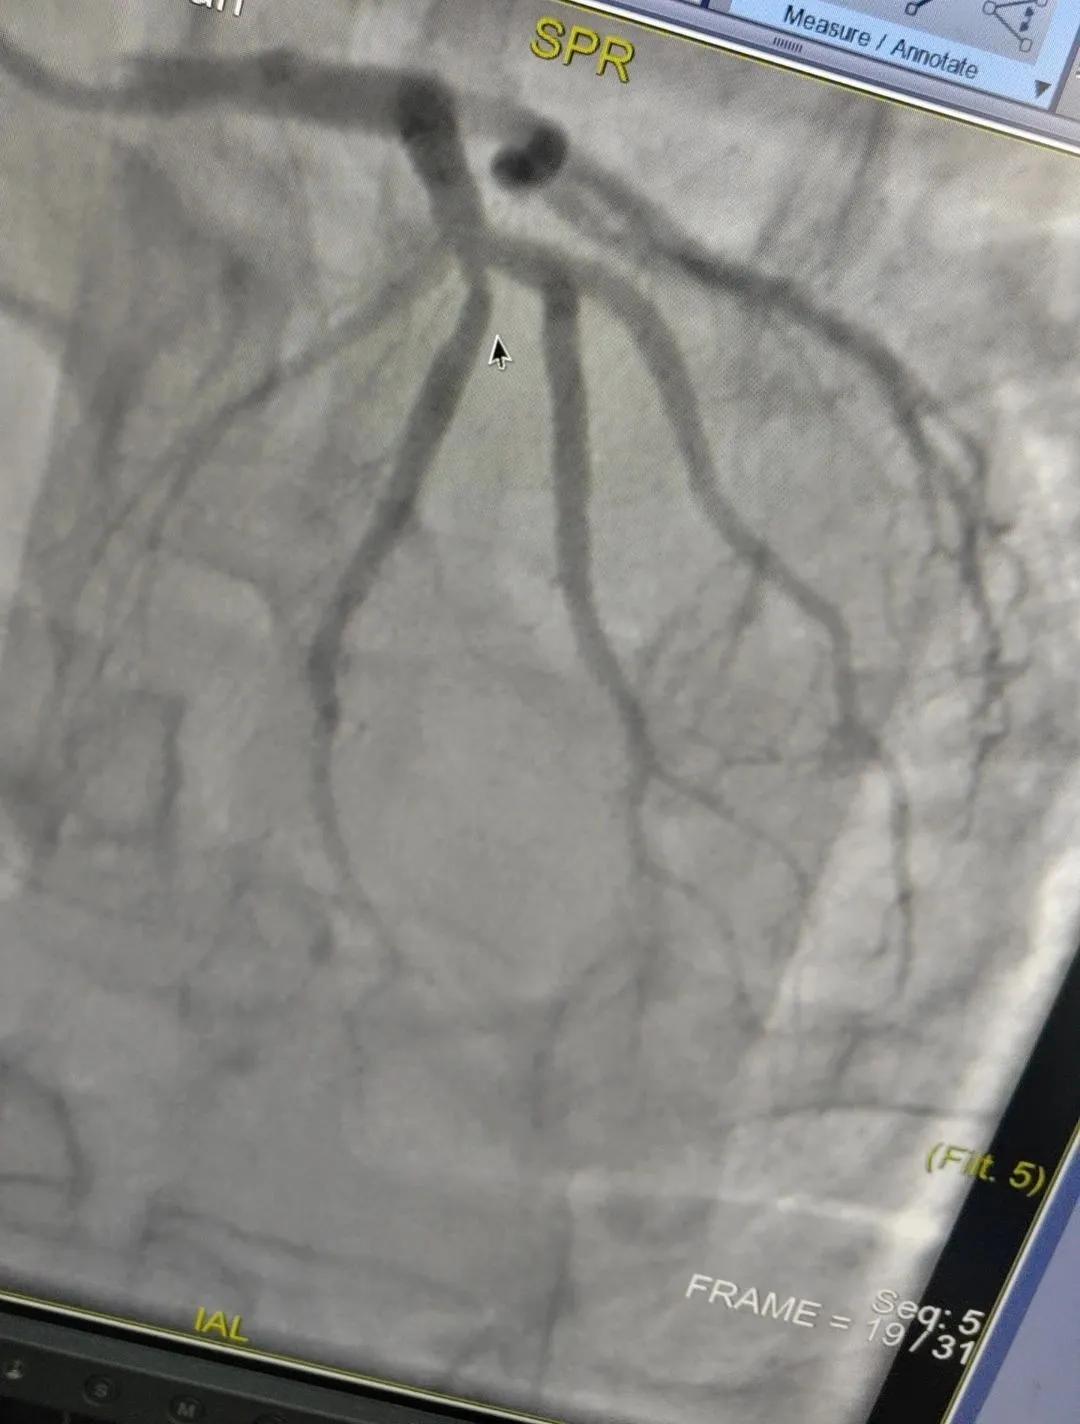

近日,漯河市中醫(yī)院成功開展了一例心腦血管聯(lián)合造影的手術(shù)。

患者男,37歲,兩周前無明顯誘因突發(fā)頭昏,伴右側(cè)肢體無力來院就診,經(jīng)過對患者病情的評估以及心內(nèi)科和腦病科醫(yī)生聯(lián)合會診,需對患者進(jìn)行心腦血管聯(lián)合造影手術(shù)。由神經(jīng)內(nèi)科楊慶堂副主任與心血管內(nèi)科陳云副主任帶領(lǐng)各自的介入團隊為該患者順利進(jìn)行了全腦血管造影術(shù)+心血管造影的介入檢查。

術(shù)中心血管造影顯示:LAD中段發(fā)出D1處可見約50%節(jié)段性狹窄,RCA中段狹窄約40%,PLA可見約70%狹窄病變。

腦血管造影顯示:左側(cè)頸內(nèi)動脈嚴(yán)重遷曲,左側(cè)大腦前動脈未顯影,左側(cè)大腦中動脈M1中段以遠(yuǎn)未顯影,M1近段串珠樣嚴(yán)重狹窄,顱底可見少量煙霧血管,后交通動脈未開放;右側(cè)頸內(nèi)動脈嚴(yán)重遷曲。右側(cè)大腦前動脈A1段嚴(yán)重遷曲。

心腦聯(lián)合造影不僅明確患者的病因和病變血管,還為下一步治療提供了有力的依據(jù)。